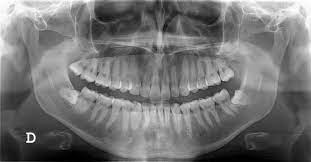

X-Ray

Digital dental radiography is a process that helps produce images of your mouth, just like a regular X-ray. In addition, it scans your mouth almost instantly and stores the digital images on a computer.

The process uses sensors connected to a computer to generate clearer gray-scale images. It makes it easier for the dentist to monitor, detect, diagnose, and treat oral diseases and conditions.

Unlike traditional X-rays that requires film to produce the image, digital dental radiography uses digital X-ray sensors to create enhanced images. It combines electronic sensors and bursts of radiation that pass through soft tissue but are reflected by bones, making them visible. There are three main methods of achieving this:

• Direct: records images through a digital sensor placed in the mouth.

• Indirect: a scanner surveys traditional dental X-rays and converts them into digital format.

• Semi-indirect: combines both digital sensor and scanner to convert an X-ray into digital images.